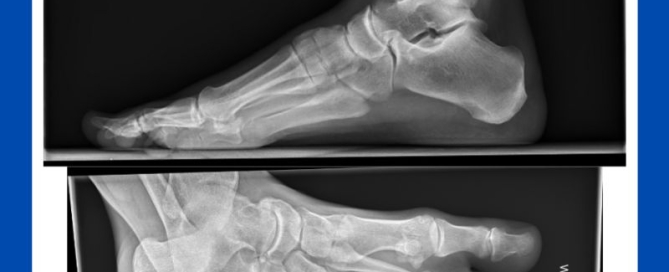

Calcaneonavicular coalition

Blog's main page This is an image from one of my cases last week. The patient is another example of the need to continue your investigations into those long-standing and [...]